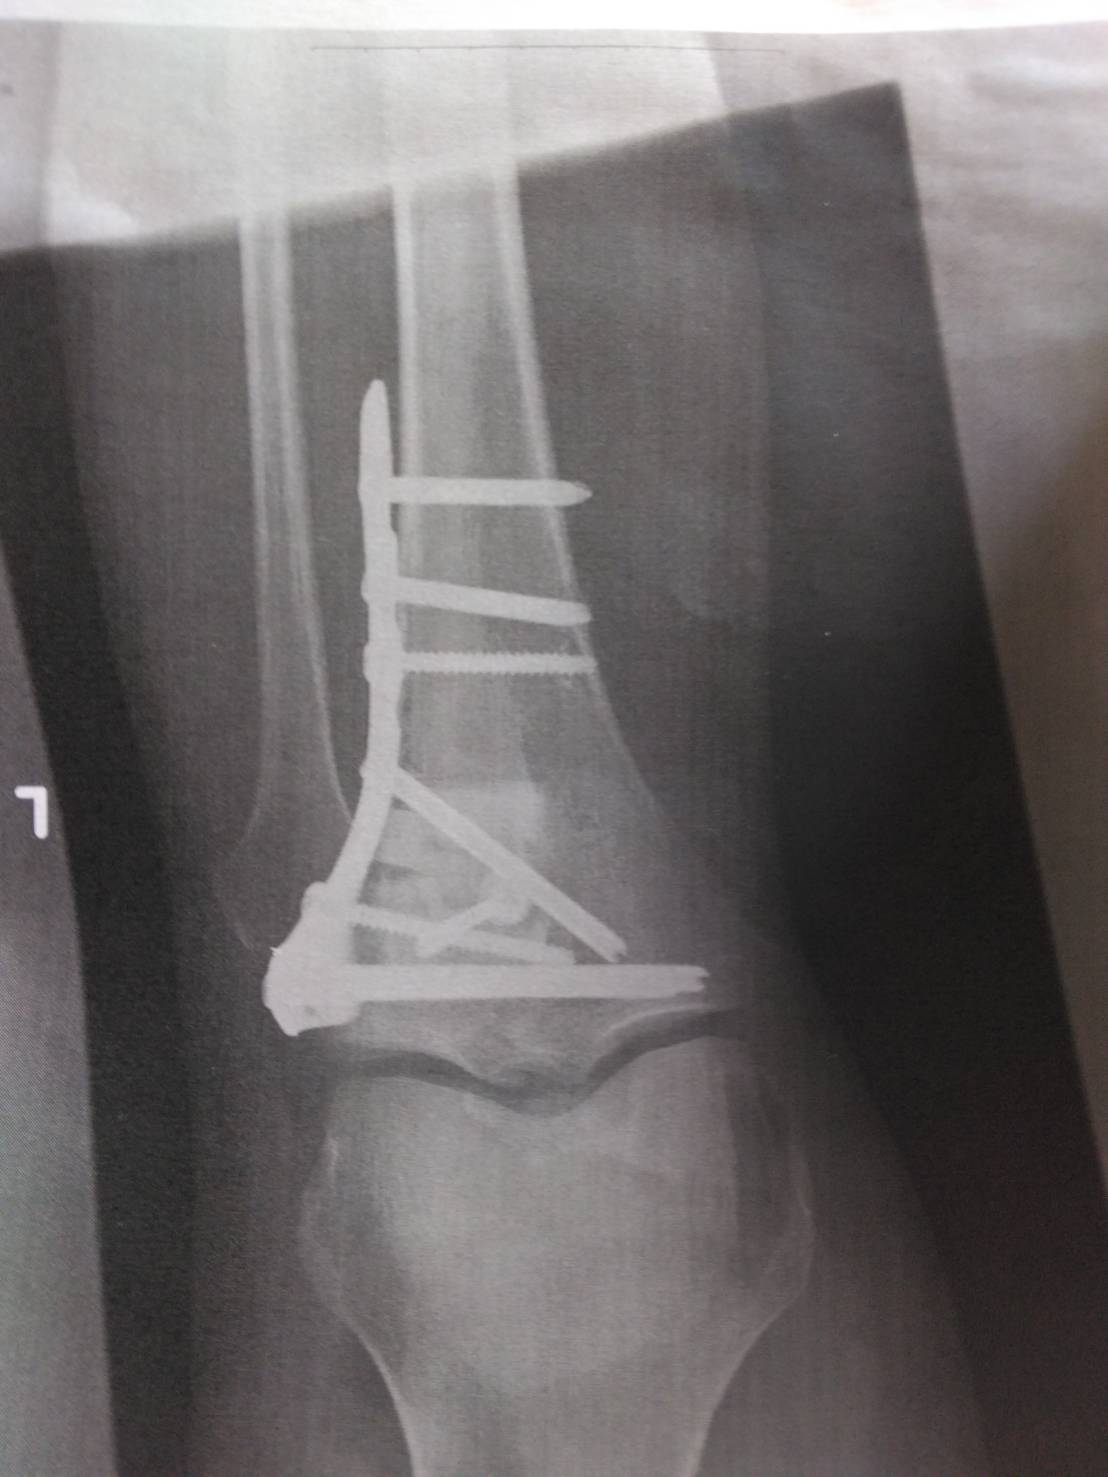

入院生活17日目――

手術無事終わったよ!全身麻酔は5秒くらいで視界がブラックアウトしてだめだった

リハビリ期間入ってるけどこれがまぁ長い…でもなんとか5/10までの退院を目指して頑張る

防御力増えたマイレフトレッグのスキャン画像置いとくね

めっちゃボルト入ってる!これ何の怪我したの?

ちなみにスキャン画像は画像の下方向が身体側なので

膝骨の下の方がグチャグチャになったからトンテンカンした感じですね

3026/04/26(日)19:44:18No.1424100729+

こう言ったらなんだけど治る怪我で良かったよ本当に

グチャり加減が後少しヒドかったら治らなかったらしいし